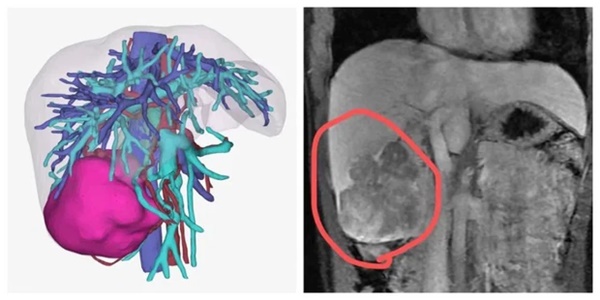

Vào ngày 9/11, sau khi xem bảng kiểm tra và chụp phim cẩn thận sau khi hội chẩn, bác sĩ cho rằng Tiểu Lý gặp vấn đề sức khỏe không nhỏ, cần nhập viện ngay. Kết quả chụp MRI cho thấy một khối rất lớn ở thùy gan phải với các tổn thương dạng nốt rải rác xung quanh. Tiểu Lý được chẩn đoán mắc bệnh ung thư gan nguyên phát.

Tái tạo 3D và hình ảnh MRI của Tiểu Lý